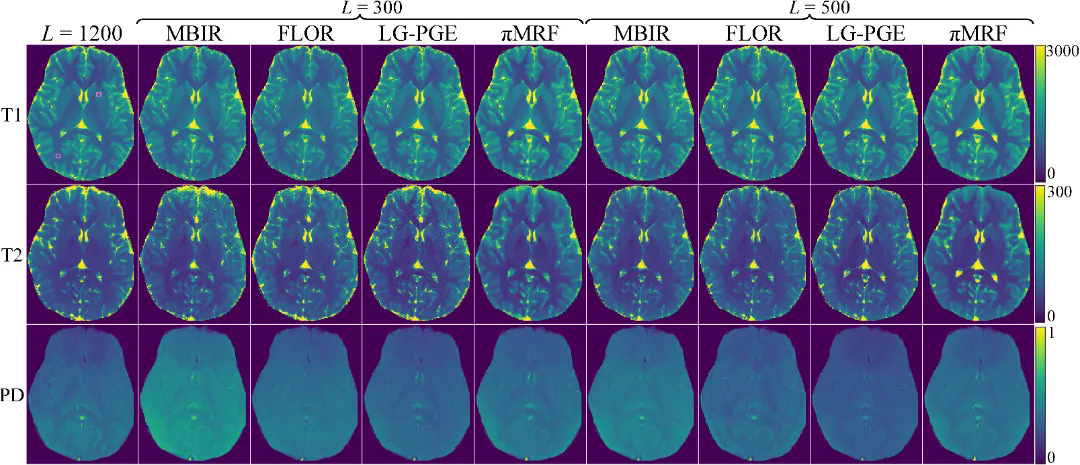

在数字仿真、水模仿体以及在体人脑实验中,πMRF在极端欠采样条件下均表现出更高的定量准确性与空间一致性,能够稳定恢复T1、T2和PD参数分布,并在组织边界及病灶区域保持更可靠的细节表达,整体性能显著优于现有对比方法。上述结果表明,该研究有效缓解了 MRF 在极端欠采样条件下面临的不适定逆问题,展示了“物理模型与连续神经表示深度融合”在复杂医学成像反演任务中的应用潜力。

图5:在体人脑实验结果